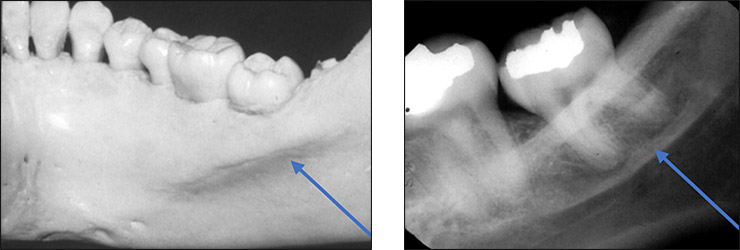

what is this, its description and its appearance on images

mental foramen

hole on external surface of mandible region

round radiolucency in apical region of mandibular premolars, may been seen intraoral